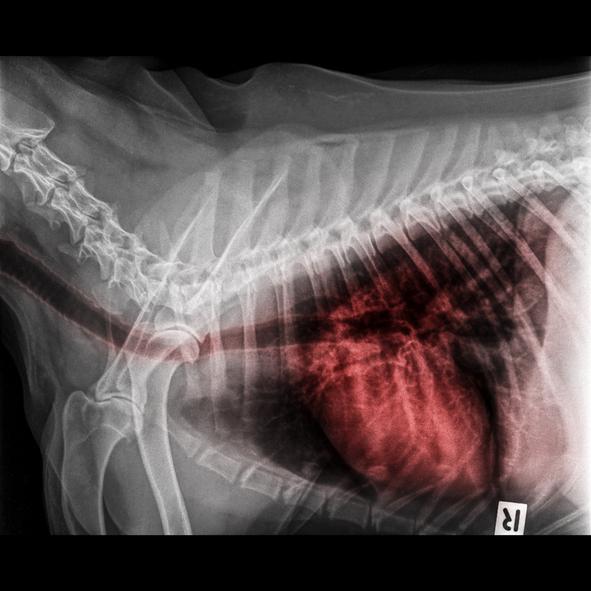

Salvo que tengamos claro cuál es la causa de la tos, por ejemplo, la presencia de humo, caso en el que tendríamos que eliminar el desencadenante, o un collar demasiado apretado que solo tendríamos que aflojar, si tu perro tiene tos seca y arcadas deberás contactar con el veterinario. Sobre todo, no utilices antitusígenos por tu cuenta. Solo este profesional puede examinar al perro y realizar las pruebas pertinentes para localizar la causa. Puede ser necesario hacer una radiografía torácica o, en los casos crónicos, un lavado intratraqueal. Y es muy importante llegar al diagnóstico, ya que de él dependerá el tratamiento.